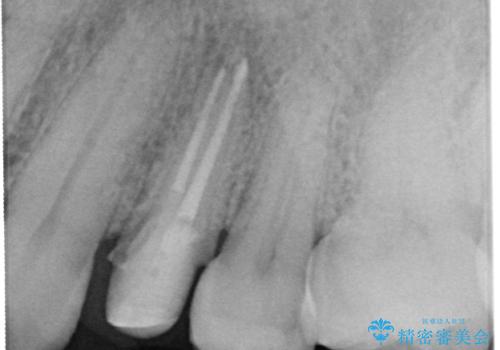

大きな虫歯で崩壊した歯の修復

- 虫歯が深かったため、根管治療を行い、土台を立て直しかぶせ物を製作します。

虫歯で奥歯が真っ黒になり崩壊していましたが、悪い部分を完全に取り除き、丁寧に修復することでまた長く機能させることができます。